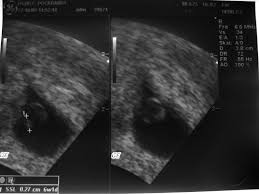

Frühe Zwillingsschwangerschaften im Ultraschall Eineiige Zwillinge in der 55 Schwangerschaftswoche. Sie sind 6 Wochen schwanger SSW 6 oder in der 7.

Abbildungen Und Graphiken Tipps Und Tricks Im Gyn Ultraschall Der Dottersack In Der Fruhschwangerschaft